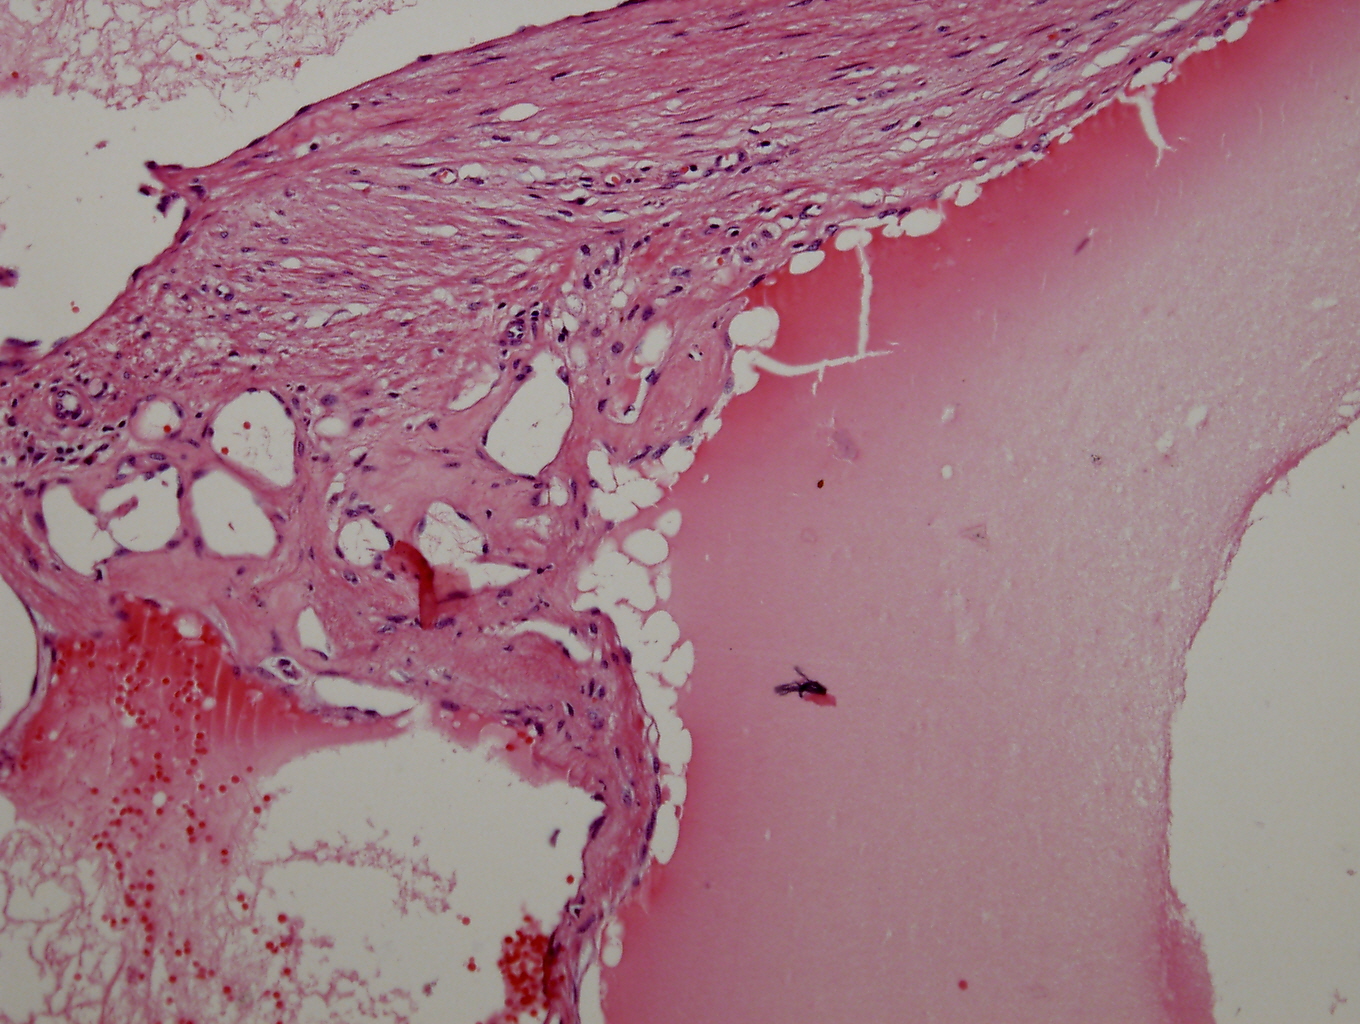

Context Adrenal cavernous hemangioma is a rare type of tumor that is usually diagnosed post-operatively. There have only been approximately 63 cases reported in the literature to date. Case report We report a case of adrenal cavernous hemangioma in a 27-year-old pregnant woman. The mass was discovered on ultrasonography when she visited a gastroenterologist for vague epigastric discomfort and vomiting. The laboratory tests were within normal limits and did not show any features suggestive of adrenal endocrinologic dysfunction. Computed Tomography (CT) revealed a well-defined 7.8 × 7.8 oval mass in the right adrenal gland with speckled calcifications. The mass was removed by transabdominal laparoscopic surgery. Strong positive immunostaining for CD31 and CD34 with weakly positive staining for podoplanin/D2-40 confirmed the diagnosis of cavernous hemangioma. Conclusions We reviewed 52 case reports of adrenal cavernous hemangioma in an attempt to identify tumor characteristics. More than half of the patients reviewed showed a heterogeneous internal structure of the mass with peripheral patchy enhancement on CT. They also showed focal or speckled calcifications either on X-ray or CT. Nevertheless, many of these characteristics overlap with the imaging phenotypes of other common diseases of the adrenal gland and therefore do not seem to provide definite evidence for differential diagnosis. Laparoscopic approach is a feasible and safe modality to remove adrenal cavernous hemangiomas because they seem to form a rigid fibrotic capsule; hence the risk of bleeding due to surgical manipulation is relatively low.

Image: Round and encapsulated fibrotic tumor.

Round and encapsulated fibrotic tumor